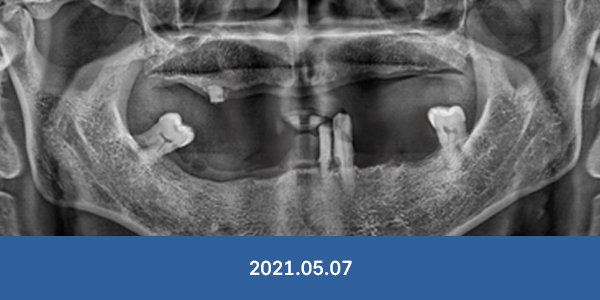

"대학병원 가보랬는데..."

서울감동치과는 가능합니다!

개원 7년간 대학병원 전원율 0% 달성

• 잇몸뼈가 완전히 없는 경우

• 전체 치아가 상실된 경우

• 치주가 심하게 녹은 경우

• 아래턱 신경과 바로 붙은 경우

※ 서울감동치과에서 실제 수술 받으신 환자분들의 사진입니다.